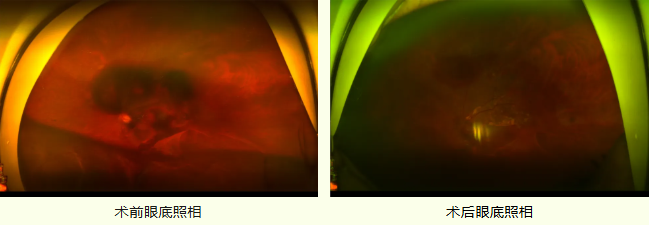

術(shù)后患者黃斑下出血基本吸收,黃斑基本恢復(fù)正常形態(tài),姜先生對(duì)手術(shù)團(tuán)隊(duì)的專(zhuān)業(yè)精神與技術(shù)水平表示深深的感謝。